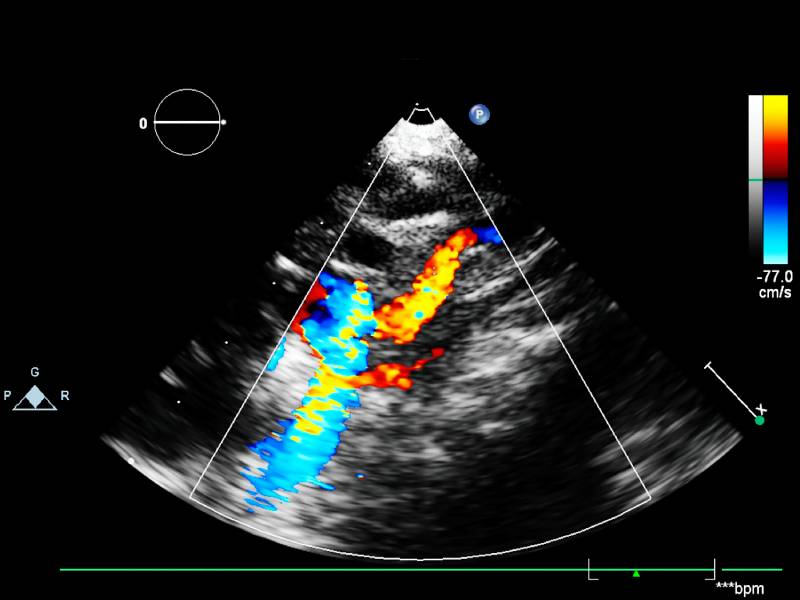

Ecocardiograma Doppler Color

El cual consiste en realizar una evaluación anatómica y funcional del corazón. Además, permite visualizar flujos sanguíneos, válvulas, cavidades, contractilidad.